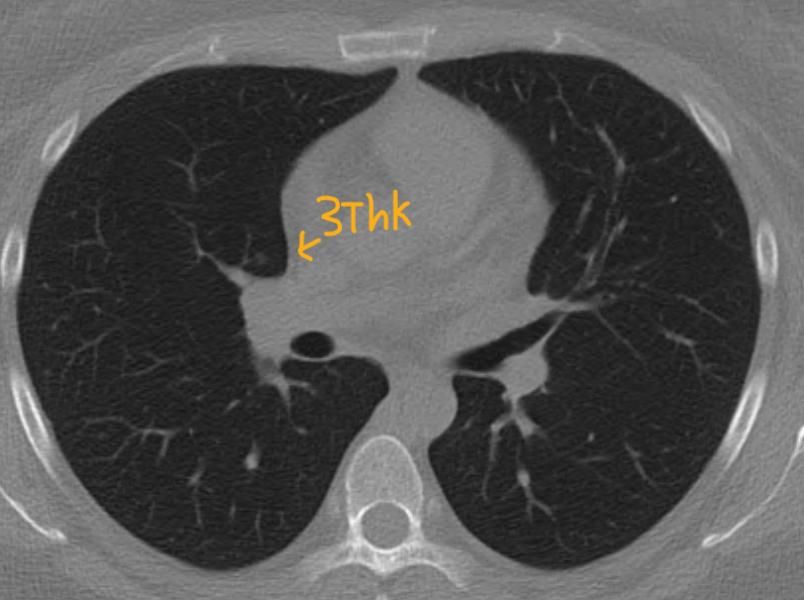

시리즈 2인 3thk만 보면서 진료를 받은거 같아요. 파란색 사진의 고형도 안나오고,

빨간색 사진의 짙음 음영 고형?반고형?간유리 결절이 안보이는 ct영상

25년 결절 판독 Little change of a tiny solid perifissural nodule in RUL (2-52).

고형이애요 간유리에요 반고형간유리 같나요